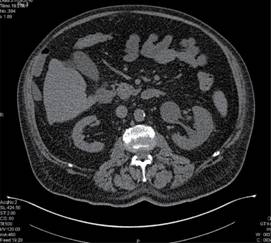

Paciente masculino de 64 años de edad, con antecedentes de importancia de hipertensión arterial sistémica, enfermedad pulmonar obstructiva crónica, hiperuricemia de larga evolución y enfermedad renal crónica de reciente diagnóstico. Se presenta al Servicio de Urgencias con cuadro gastrointestinal, fiebre, dificultad respiratoria con saturación de 70% al aire ambiente y disminución de volúmenes urinarios. Se realizan estudios de laboratorio en los cuales se hace evidente falla multiorgánica caracterizada por anemia y trombocitopenia; en el frotis sanguíneo se reportan mieloblastos y blastos, 5% en sangre periférica, con reacción leucoeritroblástica, elevación de enzimas hepáticas, elevación de azoados con anuria, persistencia de saturación de oxígeno baja (70-85%) a pesar de haberse proporcionado oxígeno suplementario por puntas nasales y posteriormente tienda facial a 10 L/min. Se decide realizar las TAC tóraco-abdominal con las siguientes alteraciones descritas en las Figuras 1, 2 y 3.

Figura 2: Adenopatías supraclaviculares derechas, axilares bilaterales a nivel de cadena mamaria interna derecha, periaórticas con pérdida de su morfología.